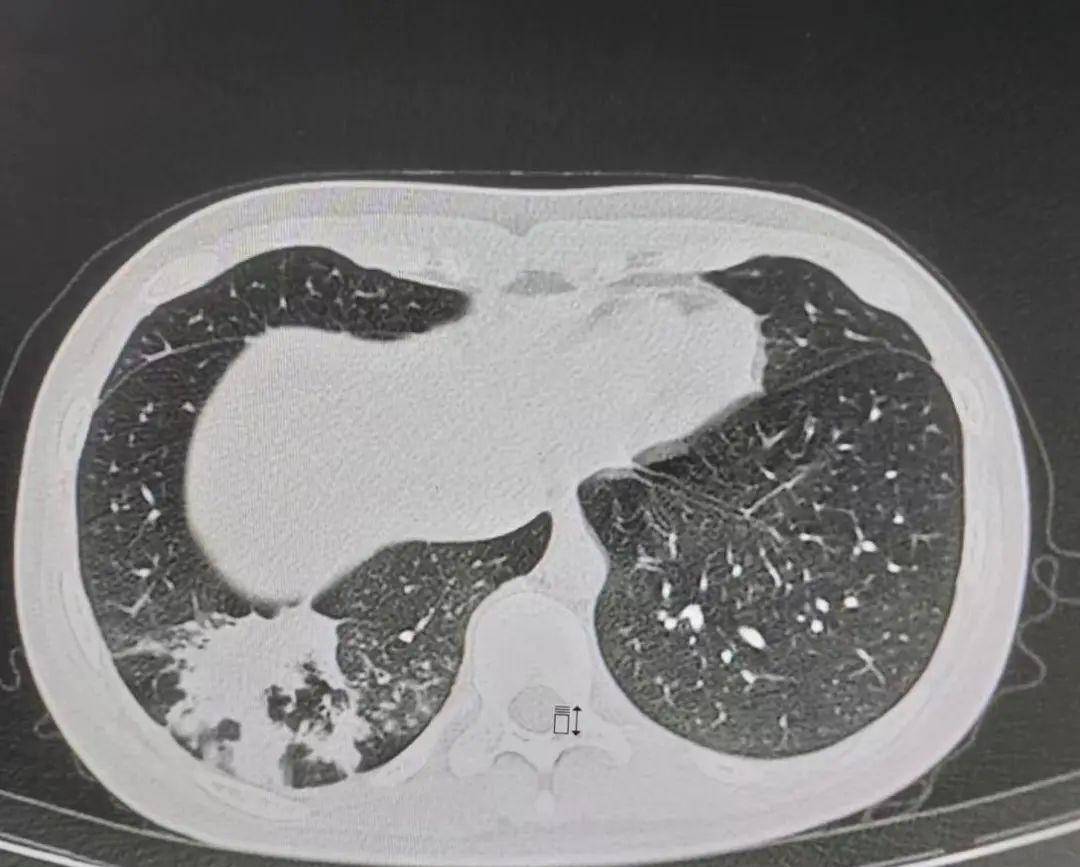

支原体肺炎肺部损害

肺炎支原体肺炎时,ct怎么看?

ct发现右侧肺炎,多发的斑片影,沿支气管周围分布(提示气道吸入性感